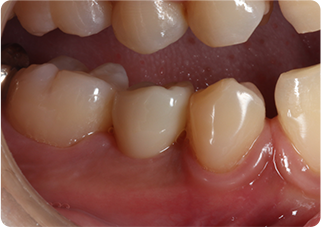

精密根管治療③

術前

術後

| 主訴 | 奥歯で噛むと痛い |

| 治療期間/回数 | 1ヵ月、4回 |

| 価格(税込) | 88,000円(税込) |

| リスク・副作用 | 病変再発、歯根破折の可能性 |

| ポイント | う蝕検知液を用い、むし歯の取り残しが無いようにし、ラバーダム防湿を行い、無菌的に根管治療を行った。根管充填材は、殺菌作用の強い保険適応外のMTAセメントを使用した。 |